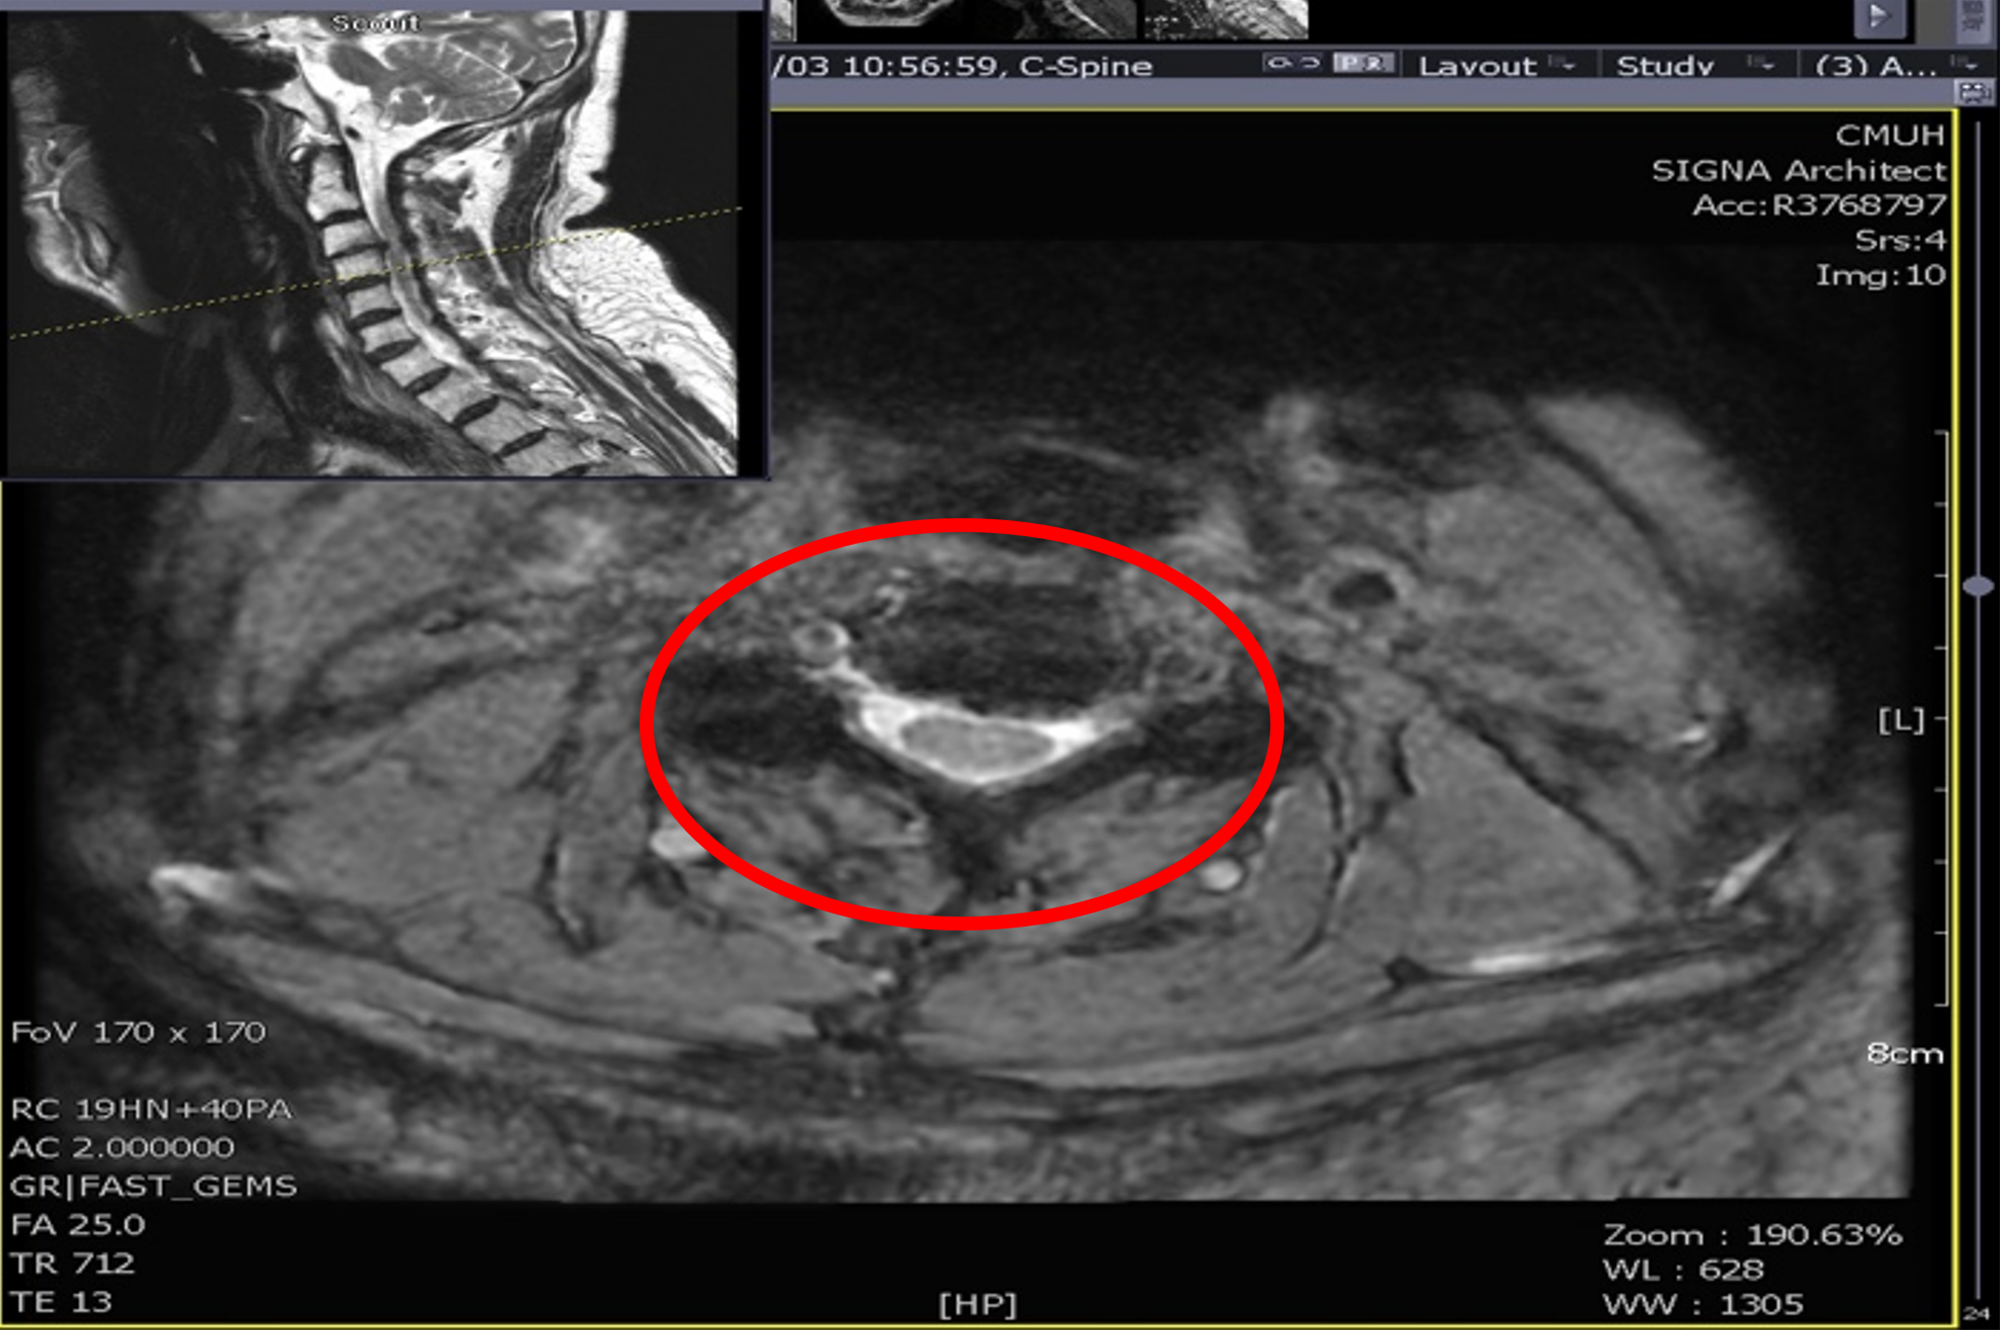

陳肇烜主任說明,患者就診時雙手明顯麻痛,右手完全無法舉起,雙腿僅能微弱抬起,已需依賴輪椅代步。影像檢查顯示其頸椎第3至第4節因外傷性椎間盤突出,造成脊髓壓迫嚴重。考量患者合併多重慢性病及長期使用抗凝血藥,手術與麻醉風險極高,若延遲治療恐導致永久性癱瘓。醫療團隊在手術前即啟動跨科整合照護,包含暫停抗凝血藥、進行心臟超音波檢查及新陳代謝科會診,確保病患在安全狀態下接受手術。

圖一:正常頸椎(上圖)應可看到完整灰色脊髓與白色腦脊髓液。病人受傷之頸椎第3/4節(上方下圖),無法看到正常脊髓與腦脊髓液。